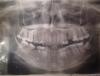

брЮл Опубликовано 30 января, 2013 Поделиться Опубликовано 30 января, 2013 (изменено) Здравствуйте!Над верхней 5й воспалилась десна.Год назад,часть зуба откололась,врач поставил 2 штифта.Через недели две после лечения, воспалилась десна над штифтом,а потом где-то через пол года и над остатком зуба.Зуб 5й слева.чуть болит, если стучать по нему.Сделанный снимок показал -надлом корня. Снимок и фото прикрепляюhttp://s019.radikal.ru/i630/1301/8f/58357cfacad2.jpghttp://s019.radikal.ru/i626/1301/7c/9c4d64e15341.jpgМне рекомендуют удаление больного зуба,но у меня страх от того,что будет видна дырка при улыбке.((((Ставить мост?Очень жалко обтачивать 2зуба.Пожалуйста, Ваши рекомендации.А также прикрепляю панорамный снимок челюсти:http://s017.radikal.ru/i401/1301/b0/5d41aea9a865.jpg' alt='5d41aea9a865.jpg'>Пожалуйста прокомментируйте,какие еще зубы нуждаются в лечении. Изменено 30 января, 2013 пользователем брЮл Ссылка на комментарий

Magdalena Опубликовано 30 января, 2013 Поделиться Опубликовано 30 января, 2013 И справа и слева 4-ки внизу перелечивать нужно и покрывать коронками. Ссылка на комментарий